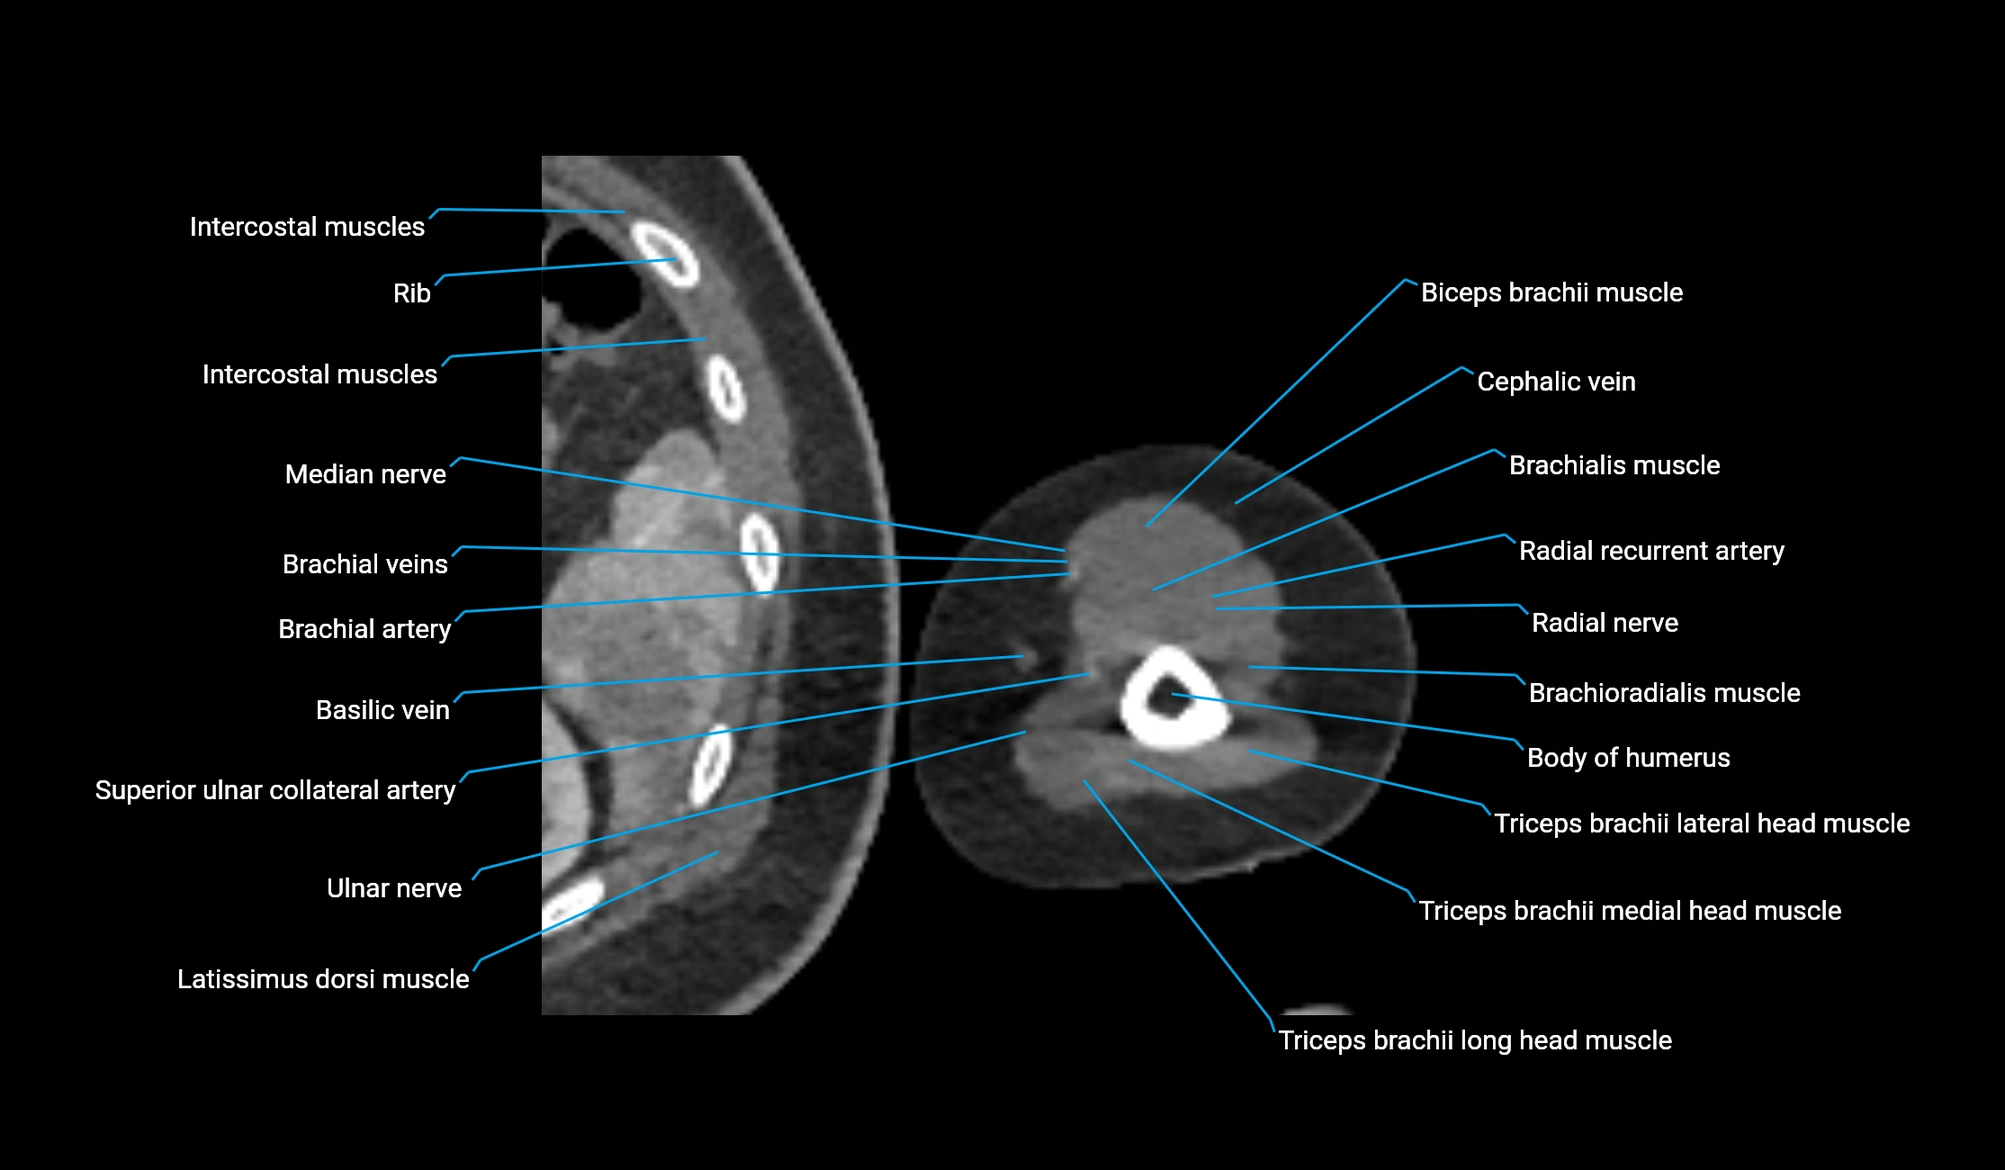

- Body of humerus

- Biceps brachii muscle

- Brachialis muscle

- Cephalic vein

- Brachial artery

- Brachioradialis muscle

- Radial nerve

- Radial recurrent artery

- Lateral head of triceps brachii muscle

- Medial head of triceps brachii muscle

- Long head of triceps brachii muscle

- Superior ulnar collateral artery

- Basilic vein

- Median nerve

- Ulnar nerve

- Latissimus dorsi tendon